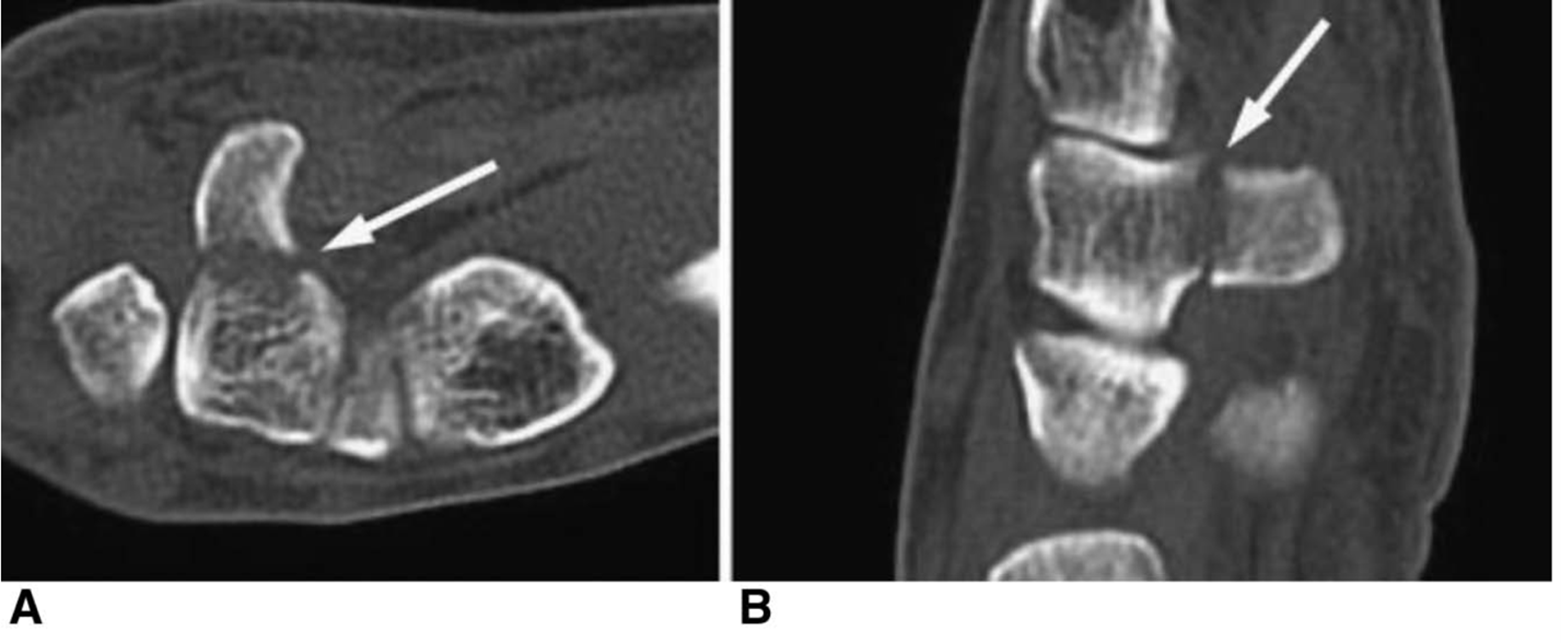

CT Scan of Hamate Fracture

CT scan showing a break in the hook of the hamate.

Reproduced from Gallant GG, Tulipan JE, Rivlin M, Ilyas AM. Baseball Injuries of the Hand and Wrist. J Am Acad Orthop Surg. 2021;29(15):648-658. doi:10.5435/JAAOS-D-20-00101